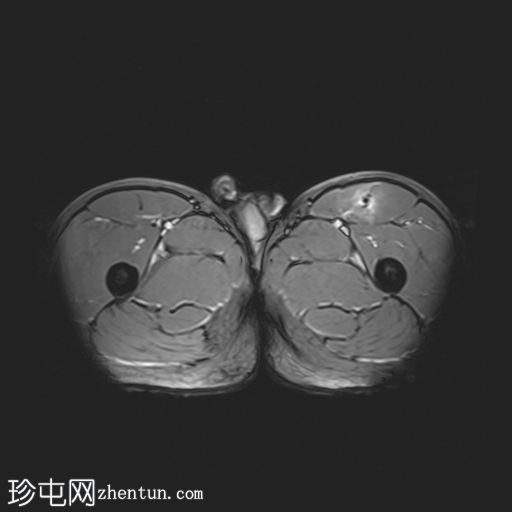

6.jpg

轴位

T2加权像

左侧股直肌近端肌腱交界处可见异常高信号,向远端延伸约至肌长一半。

可见清晰的充满液体的分离平面,呈“靶心征”,将双羽状间接头与浅表单羽状直接头分隔开,呈现出股直肌脱套样损伤的特征性影像

间接头肌纤维与近端肌腱保持连续,未见肌腱断裂或明显回缩。

可见轻度肌间及筋膜周围水肿。病例讨论